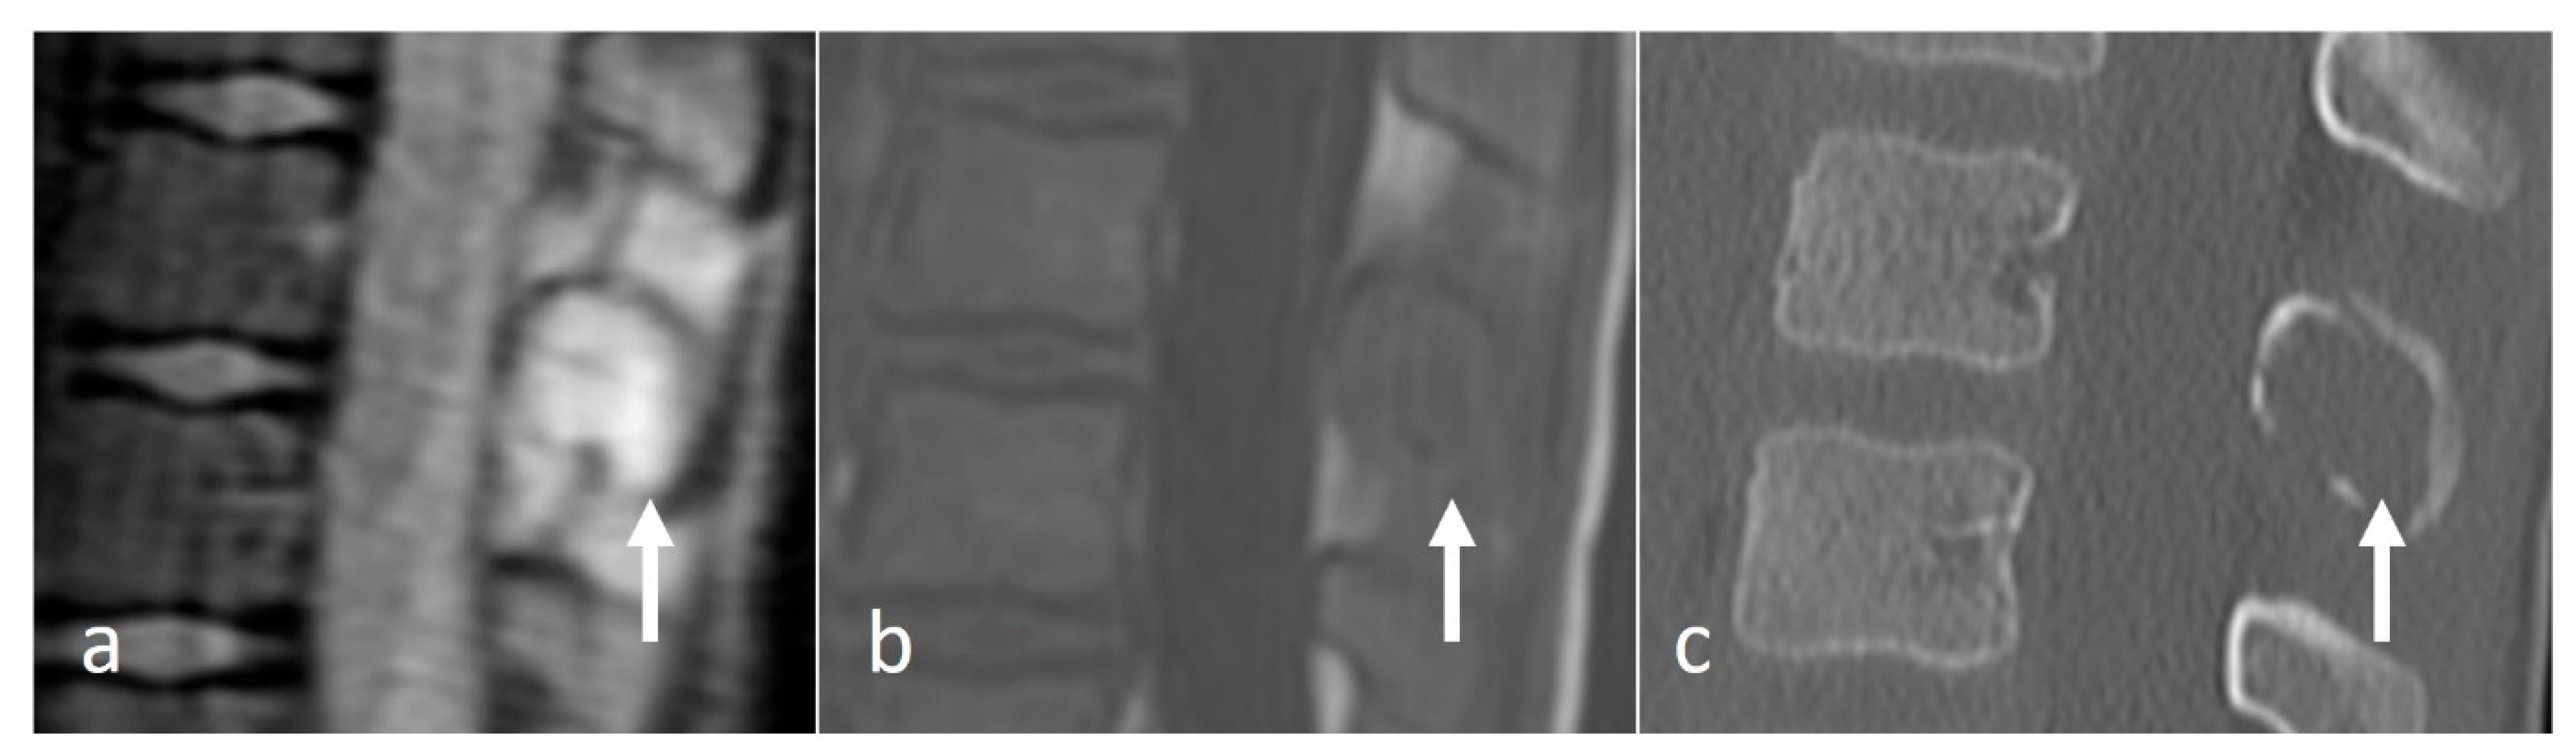

They appear as well-defined lytic lesions. Extra-osseous soft tissue components may be seen on MRI. MRI signal characteristics tend to be non-specific, with lesions being hypo- to isointense on T1 and hyperintense fluid-sensitive sequences. The lesions enhance with contrast (Figure 7a–c) [15,18].

Figure 7.

Sagittal STIR (a), T1 (b) and CT (c) images demonstrating an eosinophilic granuloma of a thoracic spinous process (white arrows) in a paediatric patient. The lytic appearance is typical of these lesions.